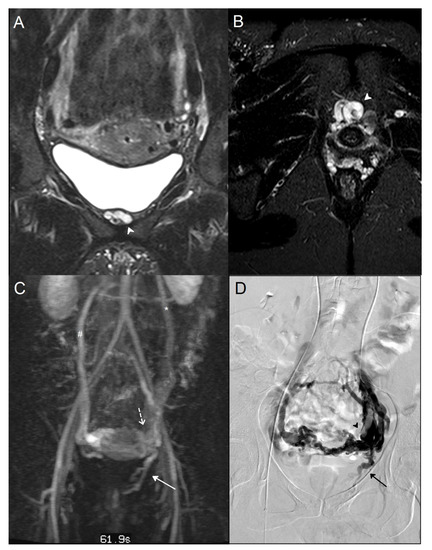

3.2. STIR and Phlebographic Findings